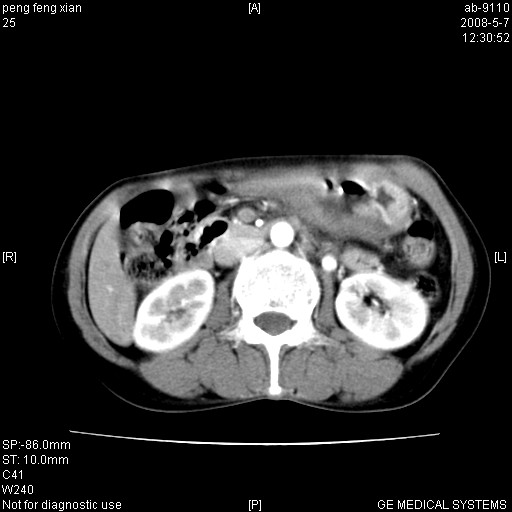

女,56岁。b超左一腹包块,考虑胃肠道肿瘤。

胃体部胃壁增厚,不均匀性强化,与胰腺分解欠情.

考虑:胃癌,胰腺受侵待除外.

鉴别:胃淋巴瘤(强化不明显)

建议:胃镜检查.